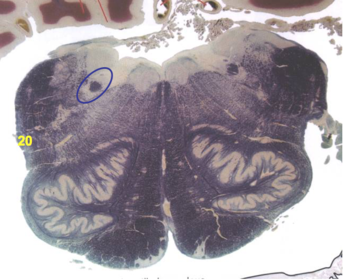

| Nucleus gracilis | |

| Accessory nucleus | |

| Medial longitudinal faciculus | |

| Pyramidal decussation | |

| Medullary pyramids | |

| Anterior spinocerebellar tract | |

| ALS | |

| Posterior spinocerebellar tract | |

| Spinal tract of V | |

| Spinal nucleus of V | |

| Nucleus cuneatus | |

| Fasciculus cuneatus | |

| Fasciculus gracilis | |

| Central canal | |